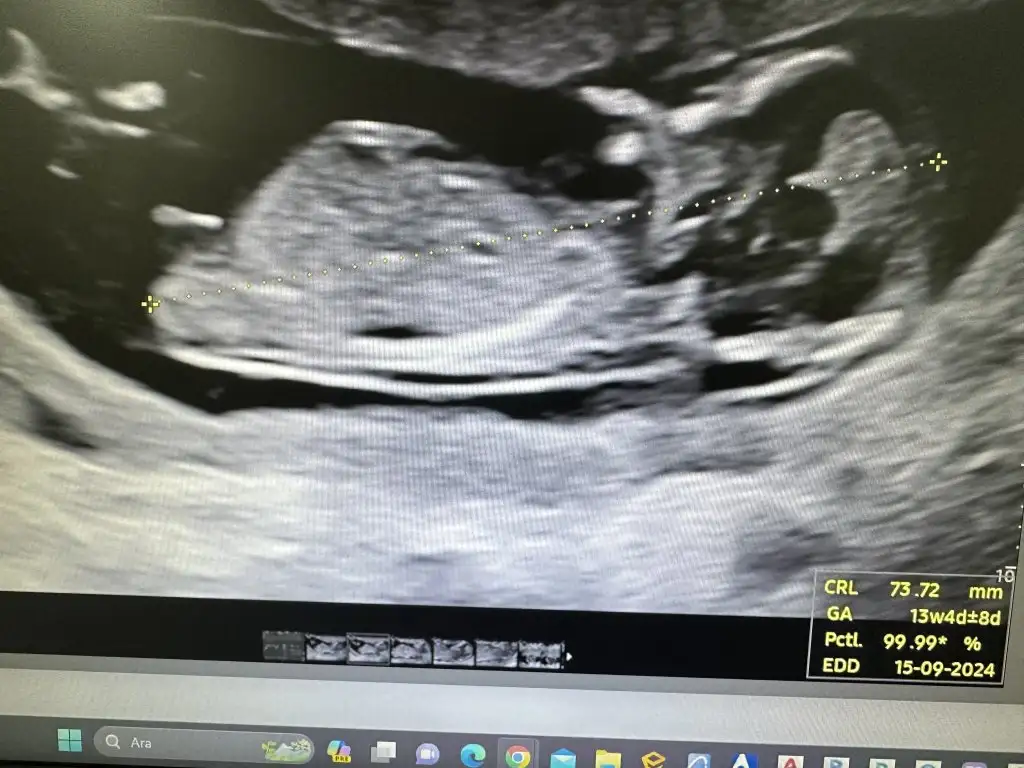

ben aslında 12+5ve 12+6 da gittim . bebegin ölçümleri 13+6 13+4 falan cıkmıs hep raporda. dediğin gibi en sondaki doktor da bebek buyuk zaten dedi. benim ilk kızım da iriydi hep önden gidiyordu ölçümleri. eşimde oyle rahatlatıyo senın kızın bile iriydi bu oğlansa zaten normal bide die.